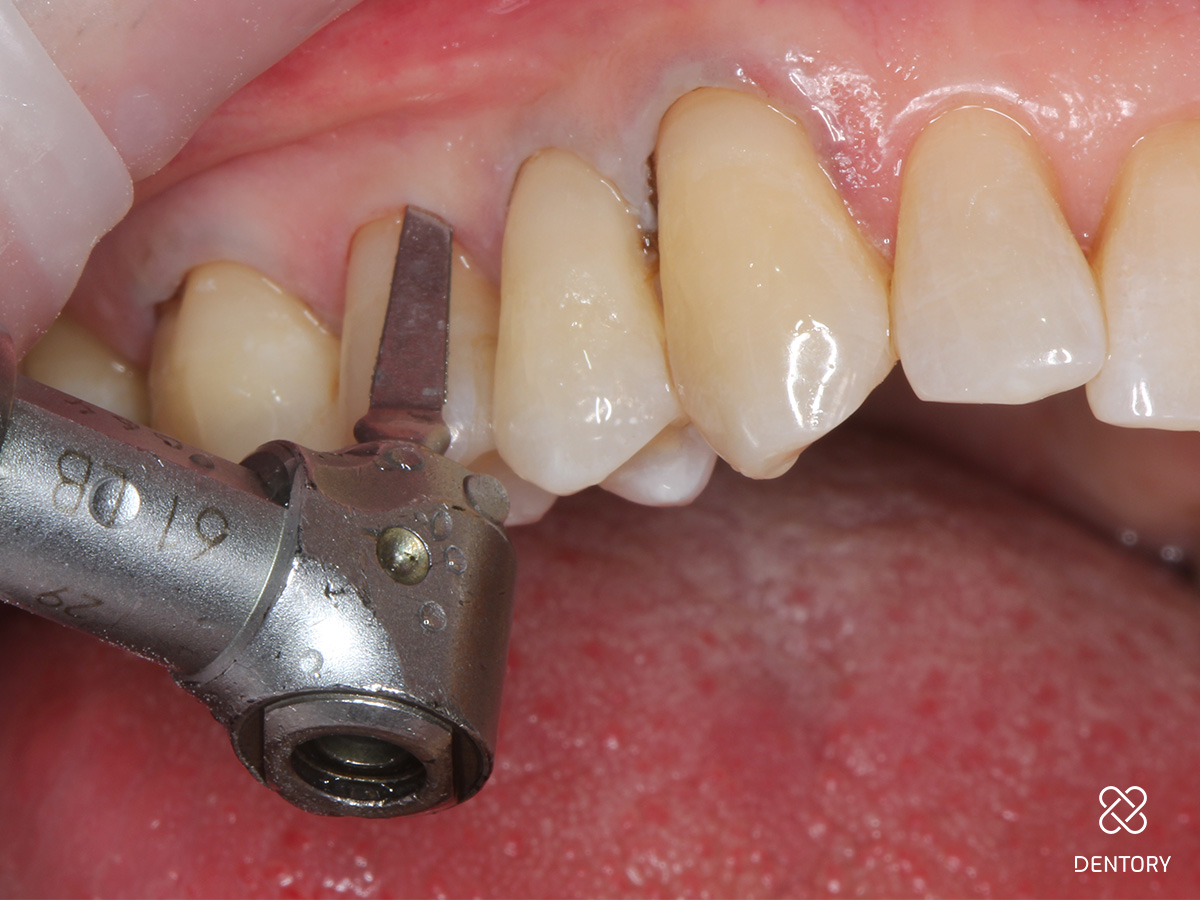

Abbildung 1

Ausgangssituation: Generalisierte Zahnhalsdefekte im Oberkiefer